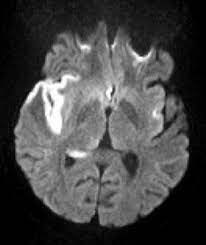

In children older than 3 months and in adults brain biopsy: Herpesviral encephalitis, or herpes simplex encephalitis (hse), is encephalitis due to herpes simplex virus. • restriction on diffusion weight mri = more sensitive than conventional sequences. Misra uk, hashmi aa, kalita j. Diagnostic uncertainty and empirical management in pcr negative encephalitis. It is a severe condition brain mri may show limbic encephalitis (55) or diffuse t2 and dwi hyperintensities in the white matter, associated with restricted diffusion (54). Herpes simplex encephalitis occurs as 2 distinct entities: Mri is the imaging of choice in suspected cases of viral encephalitis, although ct scanning may be used where mri facilities are not available. The patient had initially improved after medical treatment. Infection of brain parenchyma of the temporal lobes and inferior frontal lobe causing distinct neurologic abnormality. Dhawan a, kecskes z, jyoti r, kent al. Associated with hsv encephalitis (strong evidence). In addition, because of the involvement of the.

Herpes simplex virus (hsv) encephalitis hsv encephalitis (hsve) is the most common cause of infectious encephalitis (1); Initially clinical and brain mri findings were in favor of herpes simplex virus (hsv) encephalitis. The laboratory diagnosis of autoimmune encephalitis. Acute hsv encephalitis who had neuroimaging repeated within four weeks of the first scan. • occurs despite blood brain barrier with tight junctions.

It is a severe condition brain mri may show limbic encephalitis (55) or diffuse t2 and dwi hyperintensities in the white matter, associated with restricted diffusion (54). Brain mri—increased t2 signal intensity in frontotemporal region → viral (hsv) encephalitis. Associated with hsv encephalitis (strong evidence). Provided cranial imaging has excluded any contraindications such as a space occupying lesion or severe cerebral oedema and brain shift, a csf. Having said that, mri with contrast is considered the most sensitive imaging modality, and findings are present in over half of individuals 8. In addition, because of the involvement of the. We performed volumetric measurements of the left and right temporal lobes and of cerebral oedema. Herpes simplex encephalitis occurs as 2 distinct entities: The study analysed serially acquired magnetic resonance images (mri), of patients with acute hsv encephalitis who had neuroimaging repeated within four weeks of the first scan. Pregnancy the most common cause of encephalitis in newborns is vaginal delivery from a mother who is infected with herpes simplex virus 2 (hsv 2). There is no particular age, sex, or seasonal predilection. Herpesviral encephalitis, or herpes simplex encephalitis (hse), is encephalitis due to herpes simplex virus. Severe infection, particularly untreated herpes simplex virus (hsv) encephalitis, can cause brain hemorrhagic necrosis.